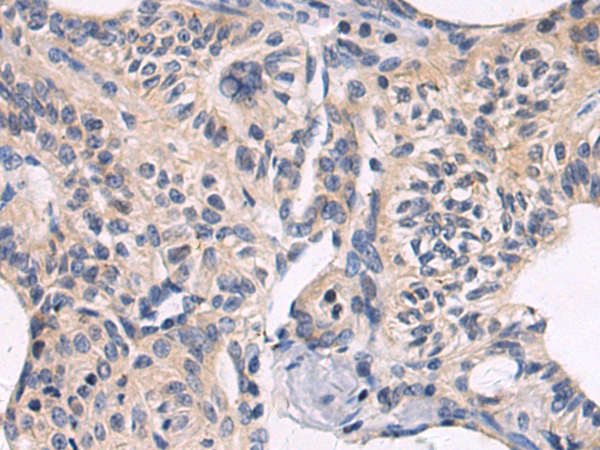

分类: 科研抗体货号: P10614别名: RIF; ARHF应用: WB,IHC反应种属: Human, Mouse